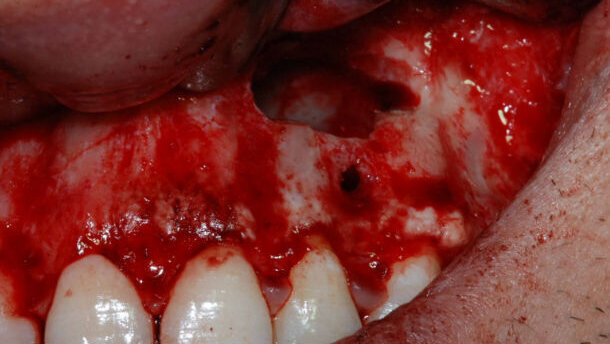

Biorivitalizzazione cutanea. a fronte di un grado di raccomandazione 1C, il suo utilizzo favorisce un’accelerazione del processo di cicatrizzazione e guarigione di ulcere croniche e ferite difficili, per l’attività biostimolante sui fibroblasti del tessuto connettivo. Queste caratteristiche hanno suggerito il suo utilizzo nella biostimolazione tissutale soprattutto in pazienti con quadri di sofferenza cutanea a seguito di esiti di chirurgia resettiva e radioterapia. L’aumento della vascolarizzazione e la stimolazione dei fibroblasti nella deposizione di nuovo collagene ha consentito di ottenere un discreto riempimento dei tessuti migliorandone elasticità, texture e trofismo (Figg. 8-10).